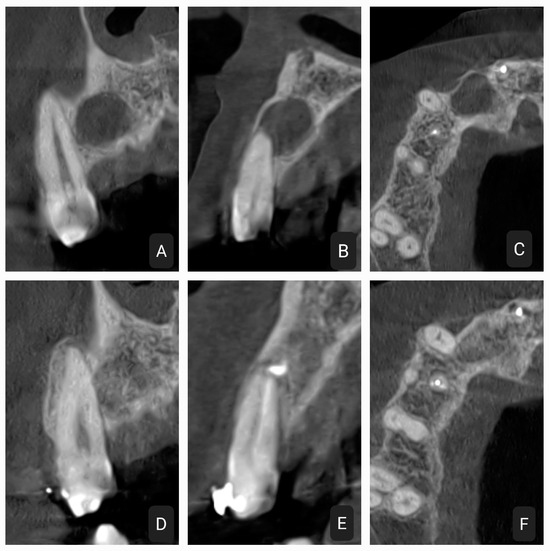

2.4. Fourth Case

2.5. Fifth Case

2.6. Control Periapical X-rays